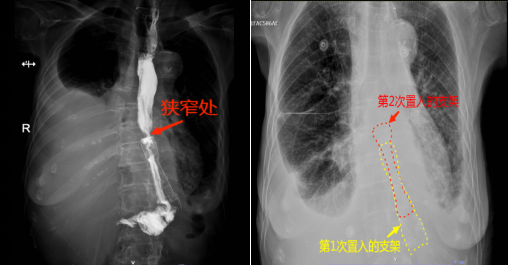

74岁的余婆婆在2013年时因胃癌行全胃切除术,但是从2022年起,她就出现了吞咽困难的情况,期间曾被诊断为食管吻合口狭窄并行内镜下食管金属支架置入术,但仅几个月后又出现了吞咽困难的情况。近期,余婆婆吞咽困难情况加重,滴水不进,身体每况日下,被家人送到91porn 阳逻院区消化内科治疗。消化内科主任金雷接诊后结合CT结果,考虑患者不能进食的原因为食管支架上方狭窄所致。消化道肿瘤术后吻合口肿瘤复发、或者吻合口周围的肉芽组织增生或瘢痕等所导致的吻合口及邻近部位的狭窄,内镜下评估狭窄部的直径<1cm,常伴有不同程度的吞咽困难。为患者完善了上消化道碘水造影检查,果不其然,上消化道造影提示,食管下段近金属支架上端入口水平明显狭窄。此时患者重度营养不良、体重不到70斤,并伴有右侧大量癌性胸水,心肺功能不全。结合患者病情,金雷为其制定了在原有食管支架上方狭窄处再叠加放置一个新的食管支架的治疗方案,重新打通这条“生命通道”,恢复患者进食,改善患者生存质量。

通过加强肠外营养支持,多次穿刺抽取胸腔积液改善肺功能后,患者精神、体力较入院时已有改善,符合手术指征。进行充分的术前准备后,金雷在消化内镜中心顺利为余婆婆进行了“内镜下食管狭窄球囊扩张术+覆膜金属支架置入术”。术后复查胸片,新放置的金属支架成功跨过狭窄处与原有金属支架上端相叠加,原本狭窄的食道再次畅通无阻。在消化内科医护专业的指导和精心的护理下,余婆婆再次品尝到了久违的食物,术后第二天即恢复了半流质饮食,吞咽顺畅再无梗阻感。目前患者恢复良好,已经顺利出院。